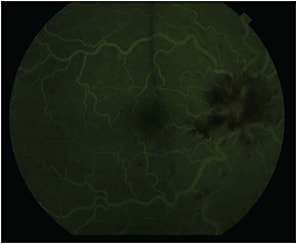

Fluorescein angiography demonstrated leakage of the disc and macula in the right eye. Macular optical coherence tomography (Carl Zeiss Meditec, Dublin, CA) showed subretinal fluid in the right eye and was normal in the left eye (Figure 2, page 62). Magnetic resonance imaging of the orbits showed no acute abnormality. His hemoglobin and hematocrit levels at the time were 7.6 and 23.7, respectively.

Figure 2. Macular OCT of right eye at presentation showing macular edema and subretinal fluid.